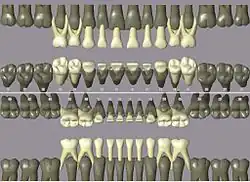

Codes, names, and usual number of roots: (see chart of teeth at Universal Numbering System)

- 11 21 51 61 maxillary central incisor 1

- 41 31 81 71 mandibular central incisor 1

- 12 22 52 62 maxillary lateral incisor 1

- 42 32 82 72 mandibular lateral incisor 1

- 13 23 53 63 maxillary canine 1

- 43 33 83 73 mandibular canine 1

- 14 24 maxillary first premolar 2

- 44 34 mandibular first premolar 1

- 15 25 maxillary second premolar 1

- 45 35 mandibular second premolar 1

- 16 26 54 64 maxillary first molar 3

- 46 36 84 74 mandibular first molar 2

- 17 27 55 65 maxillary second molar 3

- 47 37 85 75 mandibular second molar 2

- 18 28 maxillary third molar 3

- 48 38 mandibular third molar 2

ISO notation primary teeth